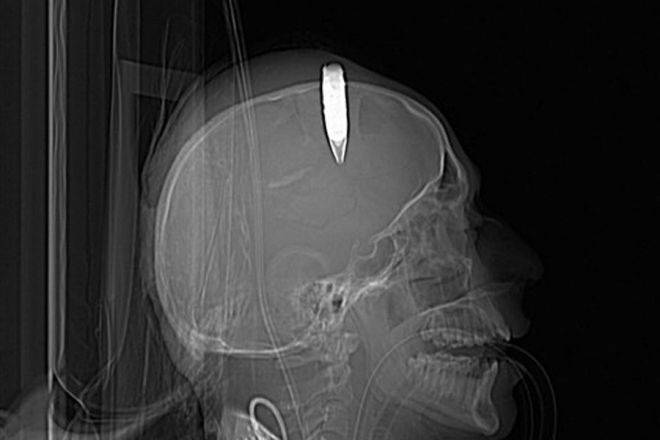

نجح فريق طبي ليبي بمستشفي على عمر عسكرلامراض وجراحة المخ والاعصاب والعمود الفقري مكون من الدكتور الإستشاري عبد الحميد بن شعبان ، الدكتـور فــرج العمامــي ، الدكتور عادل أبوزعينيـن ومساعديهم من استئصال رصاصة فى الرأس لمواطن يبلغ من العمر 22 سنة أصيب برصاصة طائشة فى دماغه متغلغلة عبر الجمجمة.

وأوضح الدكتور المشرف على العملية أن ما يميز هذه الحالة المرضية هو أن الرصاصة كانت قد أستقــرت فى منتصف الرأس من الأعلى، وفى هذه المنطقة يوجد مكـون من المكونات التشريحية للدماغ، وهو الإتساع الوريـــدي المسمـــى بـــ (Superior Sagittal sinus)، الذي عن طريقه يتم إيصال الدم الوريدي من كامل الدماغ إلى القلب، وفى حال تمت إصابة هذا المكون المهم سواء إصابة مباشرة بالرصاصة أو إصابته نتيجة التعامل مع هده الرصاصة أثناء إزالتها- فسوف يؤدي ذلك إلى نزيف حاد وقد يؤدي إلى الوفاة.